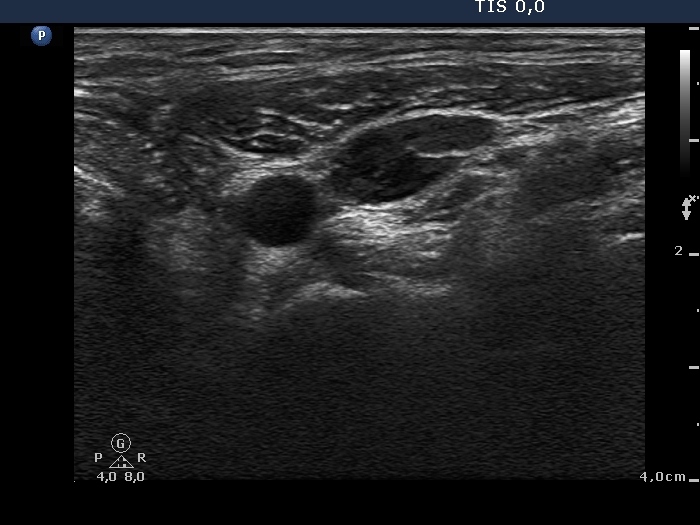

Follow-up examination 4 weeks after surgery (fourth and fifth rows):

Palpation: no abnormality.

Ultrasonography: There was no parenchyma in the thyroid beds. There were multiple enlarged lymph nodes in the lateral side of the neck. One of them very close to the thyroid seemed to be benign, reactive, but there was a chain of atypical, suspicious lymph nodes next to the strernocleidomastoid muscle.